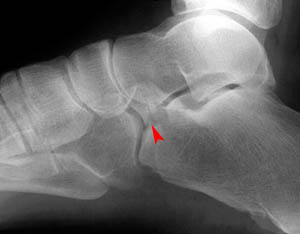

Lateral views of calcaneal fractures

Now look for the calcaneal fracture (and other abnormalities) in the image below. Can you find them? Click on the image for the answer.

Lateral view